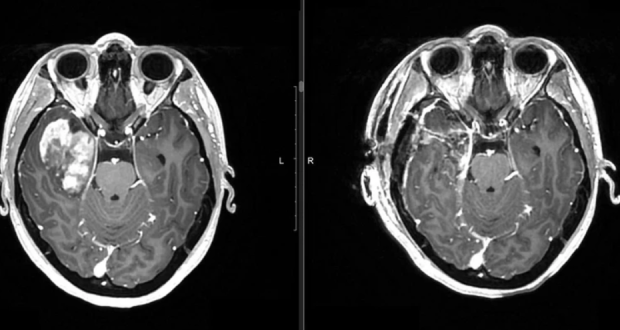

Новосибирские нейрохирурги спасли пациентку с опухолью головного мозга

В нейрохирургическом отделении №1 Новосибирского НИИТО им. Я.Л. Цивьяна успешно провели сложнейшую операцию по удалению крупного внутримозгового новообразования у 26-летней сибирячки. Около года назад у девушки появились странные симптомы. К примеру, она начала неожиданно...